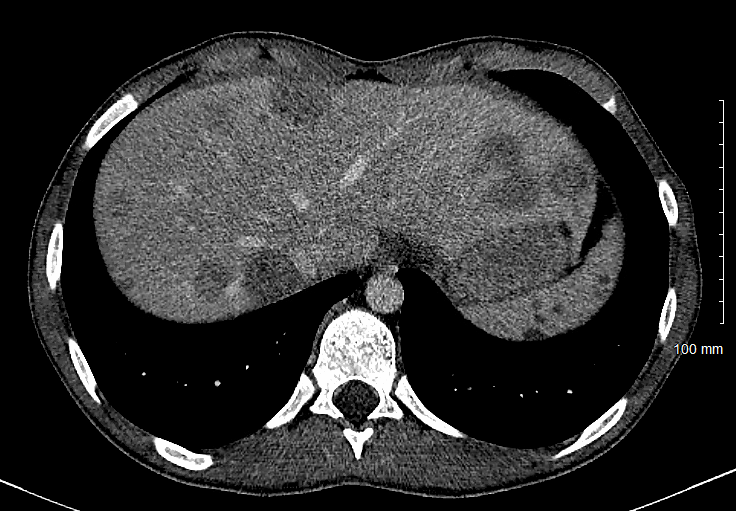

Case Presentation: A fifteen-year-old previously healthy male presented with one and a half months of intermittent right upper quadrant pain with one month of decreased appetite and weight loss. He was followed by his primary care physician who initiated an outpatient workup approximately two weeks into his disease course. A CT scan of the abdomen was obtained by the primary care physician, which noted numerous lesions in the liver and spleen. The patient was referred to the local Children’s Hospital where a broad workup was done including evaluation for infectious causes versus malignancy. The patient had no abnormal vital signs and an unremarkable physical exam. Laboratory findings were consistent with prolonged inflammation due to noted thrombocytosis and anemia of chronic disease. Biopsy was attempted by interventional radiology, but the observed lesion on CT was found to be caseated tissue and very little was able to be obtained. Shortly following this biopsy, antibody titers resulted strongly suggesting this patient had active or recent Bartonella henselae infection. He was treated with azithromycin for ten days and the patient noted rapid improvement in his symptoms.

IMAGE 1: CT of hepatic lesions